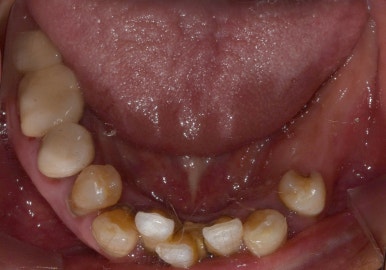

전후 사진을 보시면 텅 비어있던 왼쪽 아래부분이 임플란트 후 잘 채워져있는 것을 보실 수 있습니다.

환자분께서도 그동안 왼쪽 아래 어금니가 없으니 오른쪽으로 주로 씹느라 힘들었는데 이제 편하게 먹을 수 있어서 너무 좋다고 하시더라구요 ^^